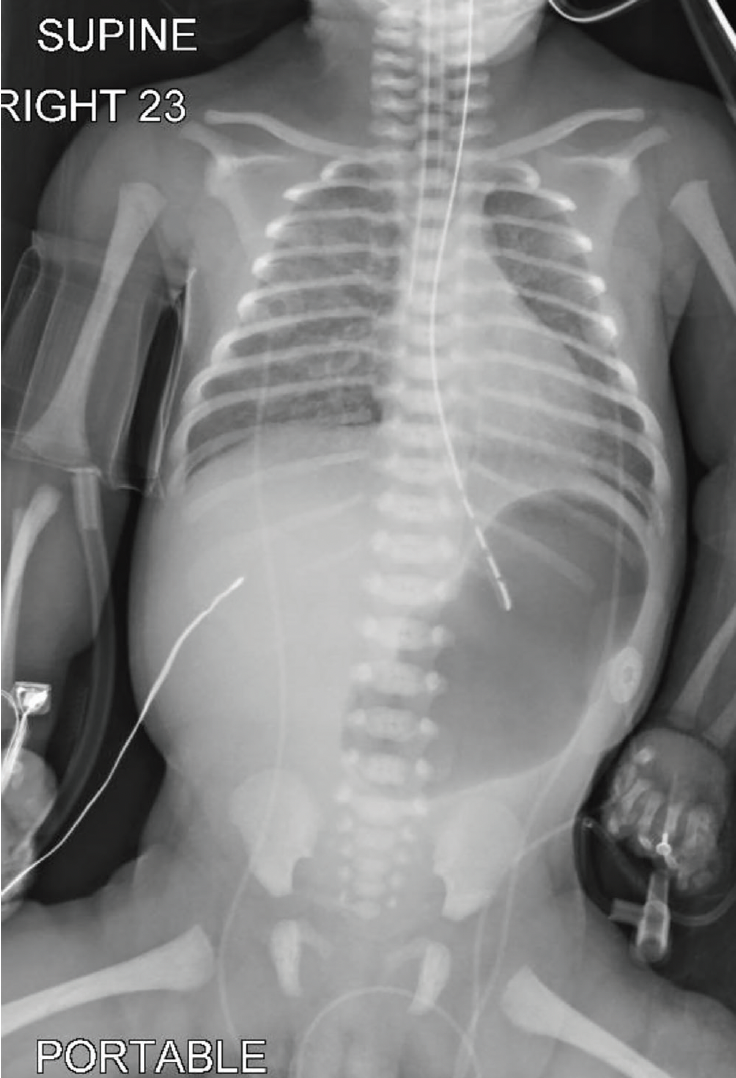

On examination, the critically ill neonate demonstrated large areas of aplasia cutis congenita involving the bilateral temporal scalp with extension onto the lateral cheeks and external ears (Figure 1). Widespread denuded skin and erosions were present on the face, neck, trunk, and extremities, developing in areas of minimal friction. The distal extremities exhibited a stocking-and-glove distribution of skin loss with apparent contractures (Figure 2). Syndactyly of multiple digits was observed. Abdominal radiography revealed marked gastric distension with paucity of distal bowel gas, findings consistent with pyloric atresia (Figure 3).